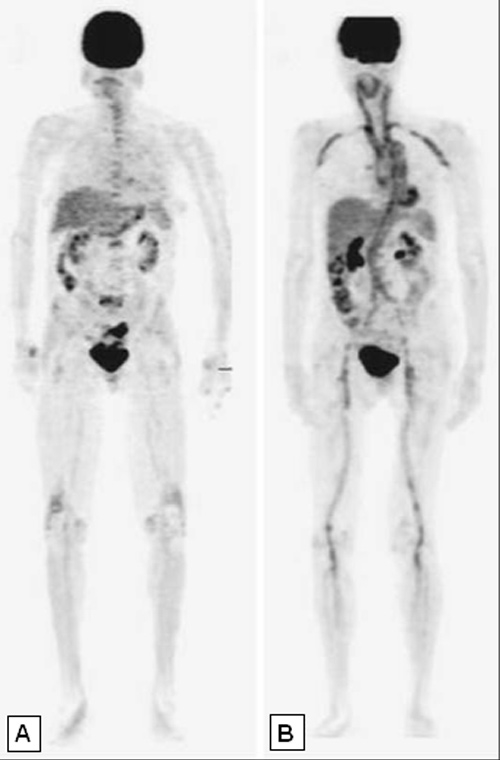

Figure 4

Whole body [18F]-FDG-PET studies. In Panel (A) a normal PET study is shown, in Panel (B) intense FDG uptake in the wall of numerous large vessels is indicative of extensive vasculitis.

PET-studies, and more recently PET/Computer Tomography (CT) studies have become a major tool for diagnosing large vessel vasculitis. Specifically, assessing 18F-fluoro-2-deoxy-D-glucose (FDG) uptake by PET is extremely helpful to assess vasculitic involvement of intrathoracic vessels (that cannot be visualized by DS)(fig. 4), and in cases of non-specific signs and symptoms compatible with large vessel vasculitis [28, 29]. Sensitivity and specificity of PET/CT to detect large vessel vasculitis in untreated patients is around 85% and 95%, respectively [28]. In steroid-treated patients sensitivity of PET studies decreases [30]. However, no data is available regarding the dose and time dependency of this effect, nor about the subgroup of patients that remains “PET-positive” despite long-term steroid-exposure.

Importantly, FDG-PET/CT-scan studies revealed aortitis – a feature classically ascribed to Takayasu arteriitis – as being present in >80% of newly diagnosed GCA patients [31], and also identified GCA as a prominent cause for fever of unknown origin (FUO) in elderly patients [32, 33]. Limitations of PET studies include its low resolution (approx. 4 mm), and the fact that pronounced FDG uptake by the CNS prevents visualisation of cranial arteries.